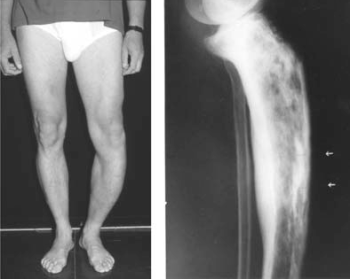

54.1.2. A csontok Paget-kórja